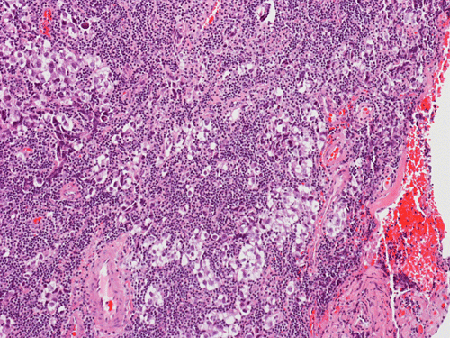

Hematoxylin & eosin

This medium-magnification photo shows the intermingled relationship between the neoplastic germinoma cells and the reactive lymphocytes.

• The tumor is highly cellular. The blood around the tumor is more likely due to the procedure than genuine hemorrhage. In some areas of the tumor, there is some necrosis which appears as pink, amorphous substances (Area  1).

• The tumor cells are surrounded by numerous lymphocytes. These are reactive lymphocytes and are mostly composed of T-cells.